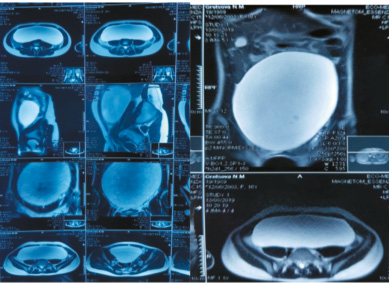

У пациентки своевременное менархе в 13 лет, менструальный цикл установился сразу, регулярный до августа 2019 г., через 28 дней, по 5 дней, менструации умеренные, безболезненные. Соматически не отягощена: перенесла ветряную оспу, острый гайморит, острую респираторную вирусную инфекцию. Семейный анамнез – без особенностей. С августа 2019 г. отметила увеличение размеров живота, задержку менструации (при отсутствии опыта половых контактов). Обратилась к гинекологу по месту жительства. По данным обследования (УЗИ и МРТ органов малого таза и брюшной полости) выявлено анэхогенное однокамерное кистозное образование размером 240¥200¥80 мм, занимающее малый таз и нижние отделы брюшной полости, с четкими, ровными контурами, тонкой капсулой, однородным жидкостным содержимым, по переднелевой поверхности опухоли на уровне верхней подвздошной ости прилежит левый яичник (рис. 1).

Рис. 1. МРТ, снимок: объемное образование, занимающее брюшную полость и малый таз.

Fig. 1. MRI, image: space-occupying mass in the abdominal cavity and small pelvis.